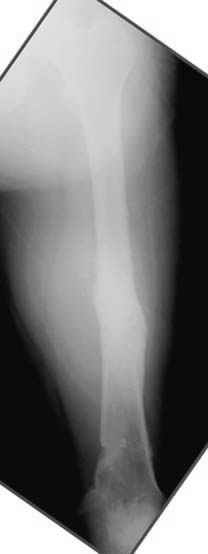

На рисунке N1 предоперационный план лечения ложного сустава шейки бедра- линия ложного сустава, угол и направление введения импланта, клиновидная остеотомия в градусах и миллиметрах, второй снимок после коррекции, расчет, на сколько удлиняется конечность и размеры импланта;

N3 рисунок окончательный снимок, после операции моя рентгенограмма должен выглядеть примерно как эта картина. На N4 снимке клин перед удалением; N5 послеоперации 3 нед.; N6 окончательная рентгенограмма.

Отправитель: Djoldas Kuldjanov 23 Ноябрь 2004, 18:21

пластическая модель; и коррекция бедра аппаратом Илизарова.

Узкий к-м канал - тонкий гвоздь- усталостный перелом дистальных винтов - развитие нестабильности и как ее результат остеолиз вокруг гвоздя - деформация анатомической оси бедра. Похоже, что я понял почему аппарат, а не новый гвоздь:-)